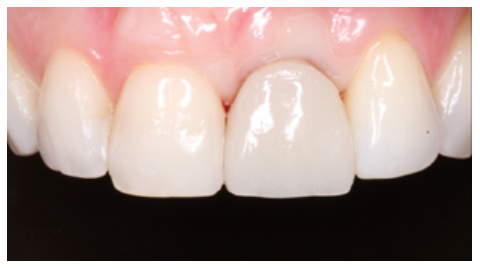

Clinical case: A 32-year-old female patient who attended for a possible root fracture of the upper left central incisor (ULCI), accompanied by a periodontal abscess at the bottom of the vestibule of the same tooth. A clinical and radiological examination established that the prognosis of the ULCI was unfavourable for conservative treatment. After evaluating the clinical features of the case, the treatment plan to extract the ULCI followed immediately by an osseointegrated implant (OII) and loading of a provisional prosthesis on the implant.

Conclusions: Rehabilitation on implants in situations of tooth loss in the aesthetic anterior sector, especially in young patients, requires a multidisciplinary treatment plan to extract the tooth and insert an OII in the correct 3-dimensional position. Various aspects need to be taken into account for this, particularly the residual remaining bone, the position of the gingival margin and preservation and conditioning of the peri-implant hard and soft tissues by means of grafts and proper handling of provisional prosthesis, until an ideal emergence profile and gingival contour is achieved before the final crown.